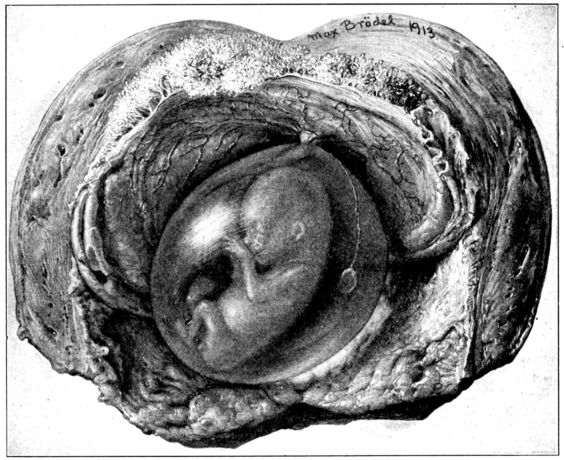

| 25. | Embryo about 5.5 cm. long in amniotic sac | 77 |